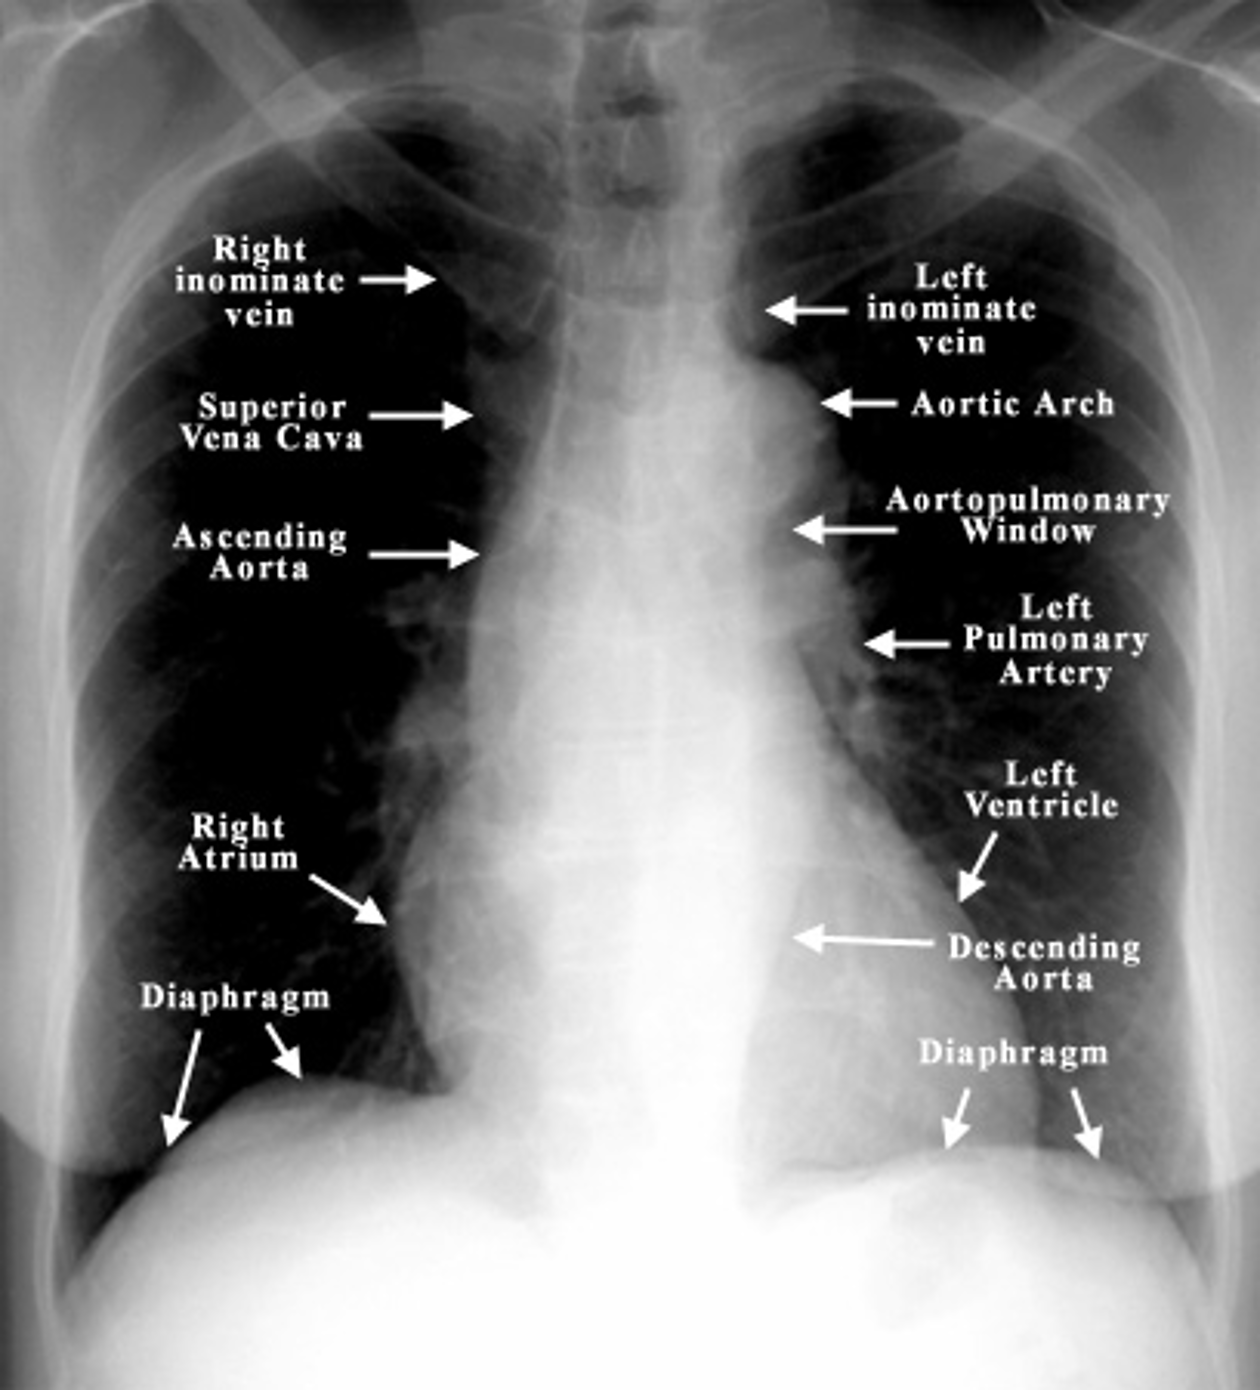

Which 3 mediastinal vessels are visible on the right side in mediastinal imaging?

brachiocephalic vessels

azygos vein

ascending aorta

Name the structures according to letter

A – Trachea

B – Clavicle

C – Right Atrium

D – Diaphragm

E – Cardiophrenic angle (Costocardio)

F – Left upper lobe

G – Gastric Bubble

H – Left Hilum